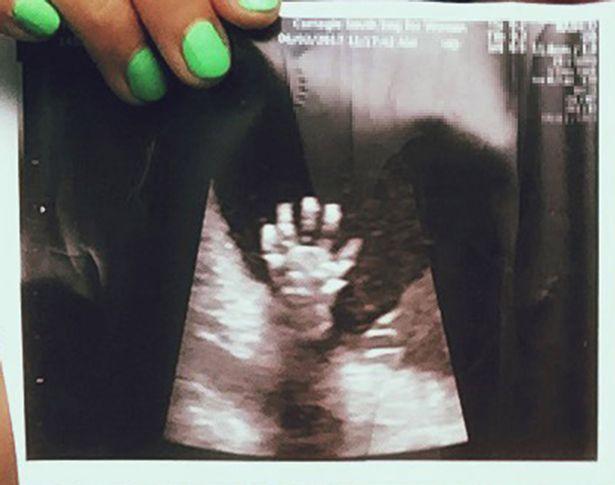

Trong lần siêu âm ở tuần thứ 20, cặp đôi vô cùng ngạc nhiên khi nhìn thấy con gái giơ cả bàn tay lên, xòe ra 5 ngón. Cặp vợ chồng đăng bức ảnh này lên mạng xã hội và nó lan truyền nhanh chóng, theo Mirror.

Bé gái giơ cả bàn tay lên, xòe ra 5 ngón

Libby, hiện đang mang thai 30 tuần, cho biết: "Bức ảnh được chia sẻ bởi rất nhiều người mang thai trên Instagram. Lần cuối tôi kiểm tra nó có 6.000 lượt thích, vì vậy tôi đoán đó là một hiện tượng, tôi cũng có rất nhiều bình luận về bức ảnh".